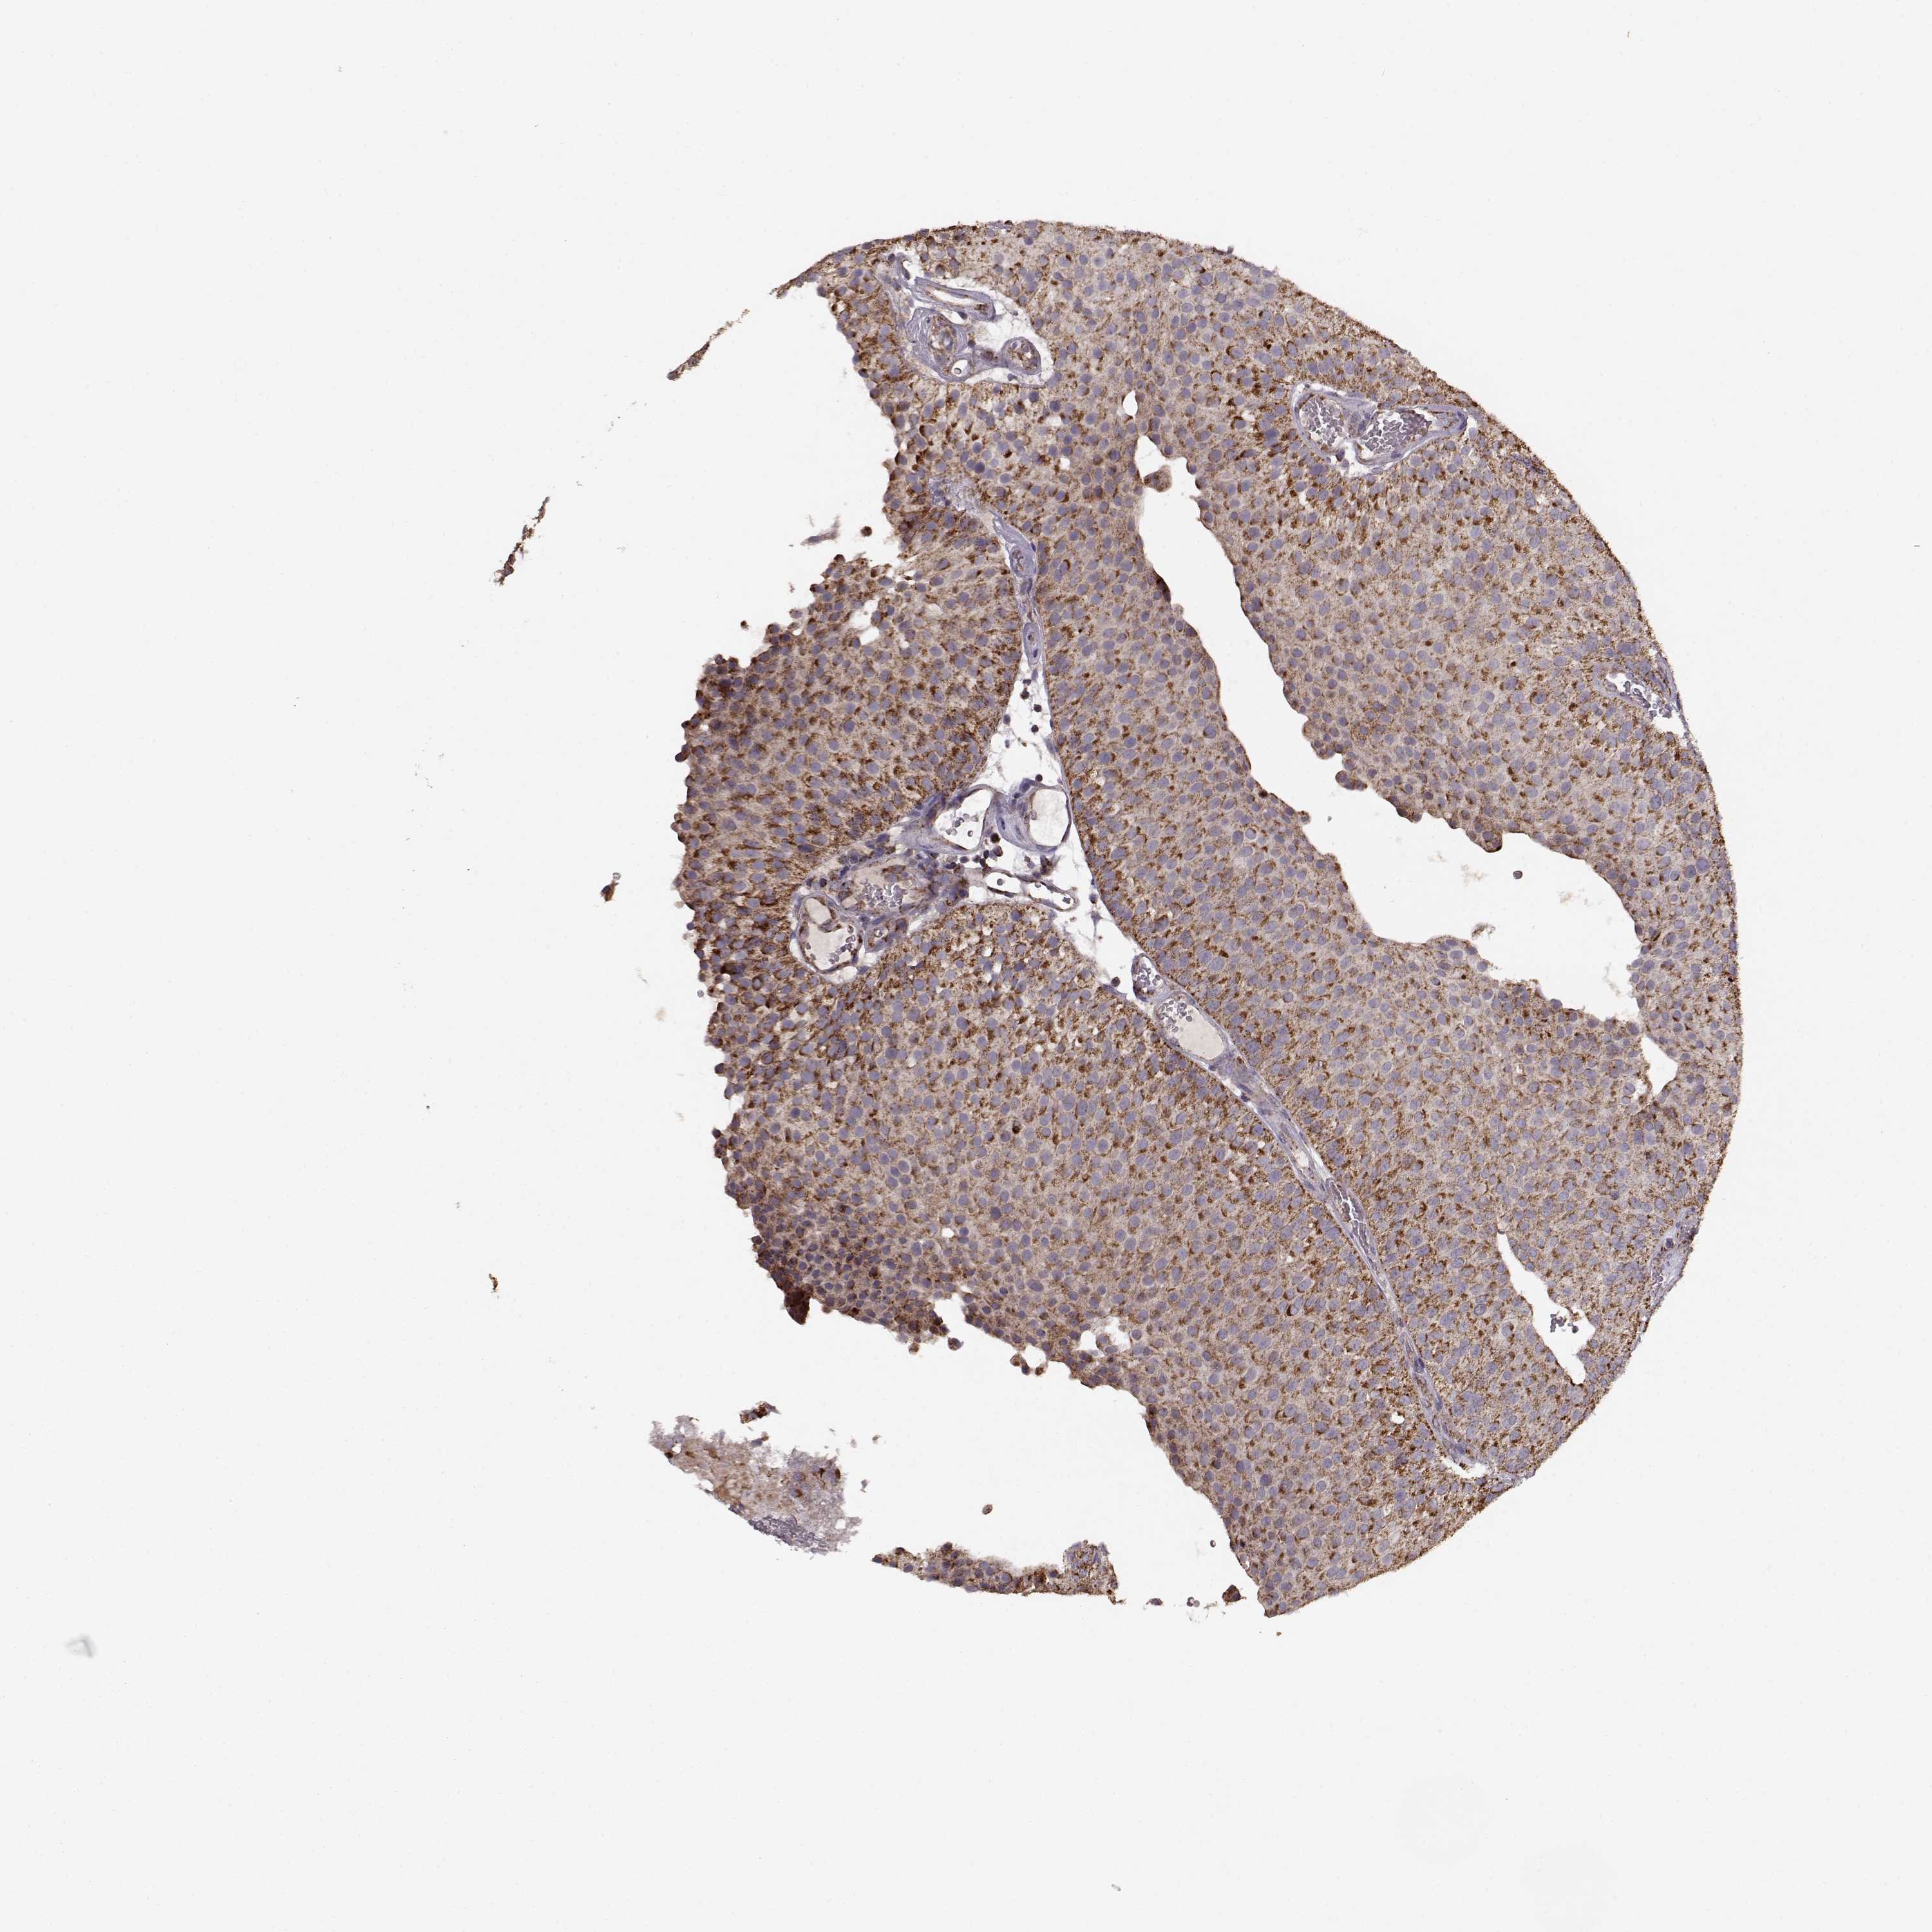

UROTHELIAL CANCER - Protein expressioni

A mouse-over function shows sample information and annotation data. Click on an image to view it in a full screen mode. Samples can be filtered based on level of antibody staining by selecting one or several of the following categories: high, medium, low and not detected. The assay and annotation is described here.

Antibody stainingi

Antibody staining in the annotated cell types in the current human tissue is reported as not detected, low, medium, or high, based on conventional immunohistochemistry profiling in selected tissues. This score is based on the combination of the staining intensity and fraction of stained cells.

Each image is clickable and will lead to virtual microscopy that enables deeper exploration of all samples and also displays staining intensity scores, fraction scores and subcellular localization as well as patient and tissue information for each sample.

Antibody HPA072695

Staining

High

Medium

Low

Not detected

Intensity

Strong

Moderate

Weak

Negative

Quantity

>75%

75%-25%

<25%

None

Location

Nuclear

Cytoplasmic/membranous

Cytoplasmic/membranous,nuclear

Urothelial carcinoma, High grade

Urothelial carcinoma, NOS

Urothelial carcinoma, Low grade